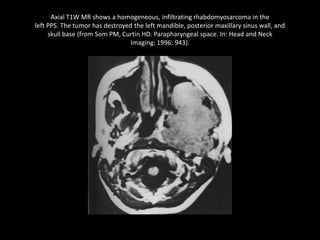

Axial T1W MR shows a homogeneous, infiltrating rhabdomyosarcoma in the

left PPS. The tumor has destroyed the left mandible, posterior maxillary sinus wall, and

skull base (from Som PM, Curtin HD. Parapharyngeal space. In: Head and Neck

Imaging: 1996: 943).

Axial T1W MRshows a homogeneous, infiltrating rhabdomyosarcoma in the left PPS. The tumor has destroyed the left mandible, posterior maxillary sinus wall, and skull base (from Som PM, Curtin HD. Parapharyngeal space. In: Head and Neck Imaging: 1996: 943).